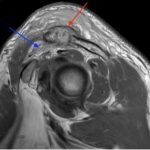

Septic arthritis of native joints is uncommon, but the condition can be threatening to life and limb if left untreated.1 Septic arthritis of the acromioclavicular (AC) joint of the shoulder is particularly rare and has only appeared sparsely in medical literature, mainly through individual case reports. Early recognition and treatment of the condition is vital, but diagnosis of septic AC arthritis can be difficult due to its presentation with vague symptoms and nonspecific laboratory findings. This case report describes the care of a patient with poorly managed diabetes who presented to the emergency department with one month of pain and swelling of the left shoulder and two weeks of pain and swelling in the right ankle. Imaging revealed fluid in the AC joint, and laboratory evaluation showed an elevation in inflammatory markers, including leukocyte count, C-reactive protein (CRP), and erythrocyte sedimentation rate (ESR). The patient’s hospital course was complicated by methicillin-sensitive Staphylococcus Aureus bacteremia without evidence of sepsis. The patient underwent open debridement and washout of both the ankle and AC joint without complication. After recovery, the patient was discharged to a rehabilitative center with IV antibiotics and weekly follow up care with infectious disease specialists. This case illustrates the importance of early diagnosis and treatment of septic arthritis, even in less common joint spaces, to prevent progression of this dangerous disease.